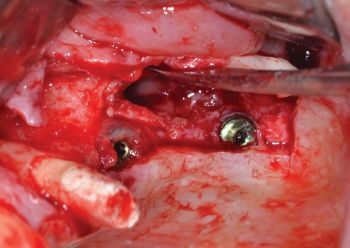

A full-thickness access flap was raised, including a crestal incision within the attached gingiva and two slightly divergent vertical releasing incisions, in order to expose the anterior-lateral wall of the maxillary sinus.

An antrostomy was created using piezoelectric ultrasonic tips to allow direct access to the sinus cavity (Fig. 7).

The antrostomy was progressively enlarged in both mesial and cranial directions using an ultrasonic tip to improve intraoperative visibility and facilitate localization of the implant (Figs. 8–10).